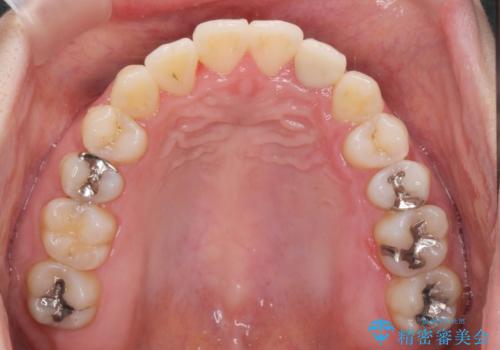

引っ込んだ前歯を並べたい マウスピースと部分ワイヤーのコンビネーション矯正

- 引っ込んで生えてしまっている前歯を並べたい、と矯正治療を希望され来院されました。

まずマウスピース矯正インビザラインシステムで、引っ込んだ歯が並ぶためのスペースを作ったのち、部分ワイヤー矯正を行い短期間での配列を計画します。

マウスピース・ワイヤーそれぞれの長所をうまく活かすことで治療期間の短縮が可能となります。

このように前歯の部分ワイヤーは引っ込んでしまった前歯や がたつきを素早く改善することができます。